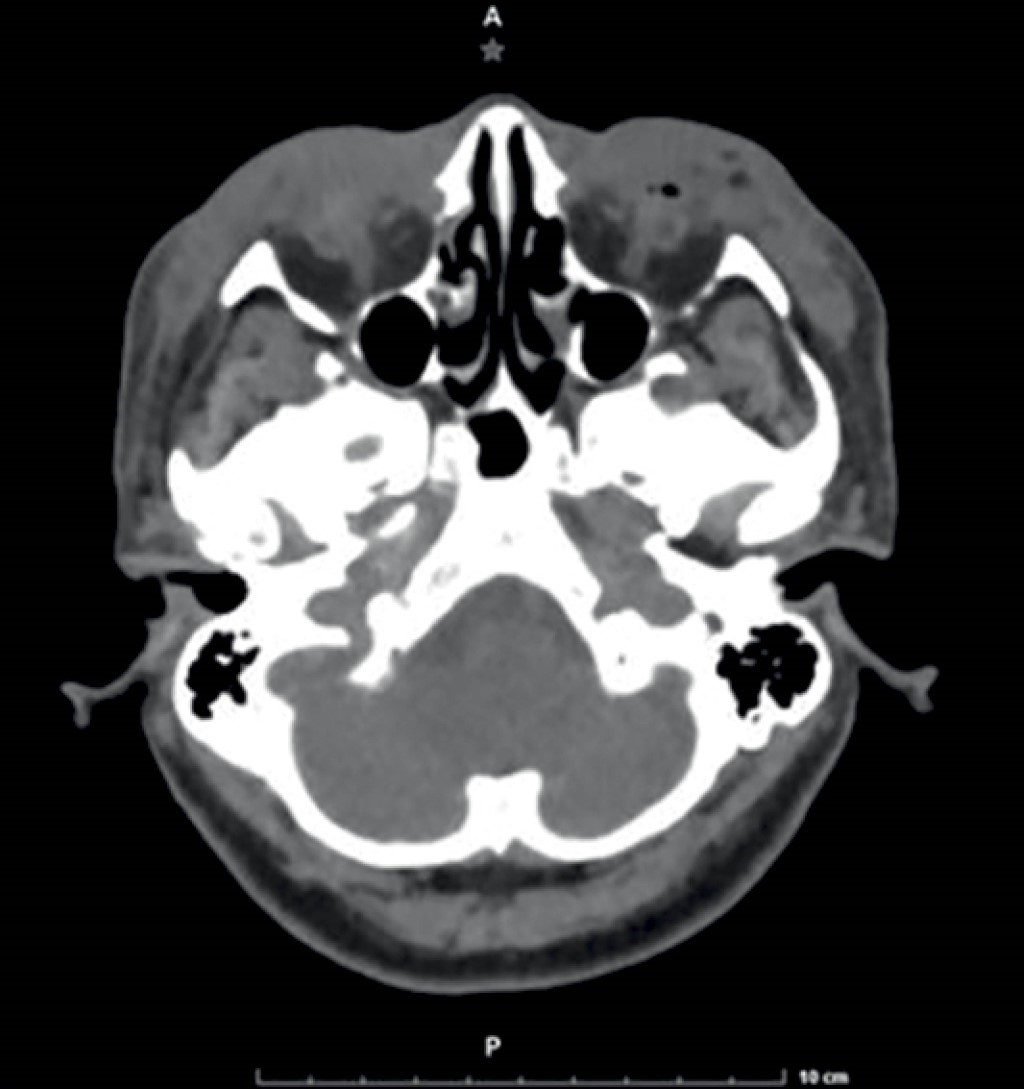

Atypical mycobacterial infection after fat transfer procedures in facial plastic surgery

Facial autologous fat injections have become one of the most important rejuvenating surgeries of our time. This has been accompanied by a rise in atypical mycobacteria infections. These soft tissue infections result from using non sterilized water or surgical equipment and can have devastating consequences if not treated promptly. Atypical mycobacterial infections are very difficult to diagnose and treat adequately. We present the case of a patient who underwent eyelid rejuvenation surgery with fat transfer and developed such an infection. A comprehensive diagnostic and treatment algorithm is proposed.

Figure 1

Figure 2

Figure 3

Figure 4

Figure 5